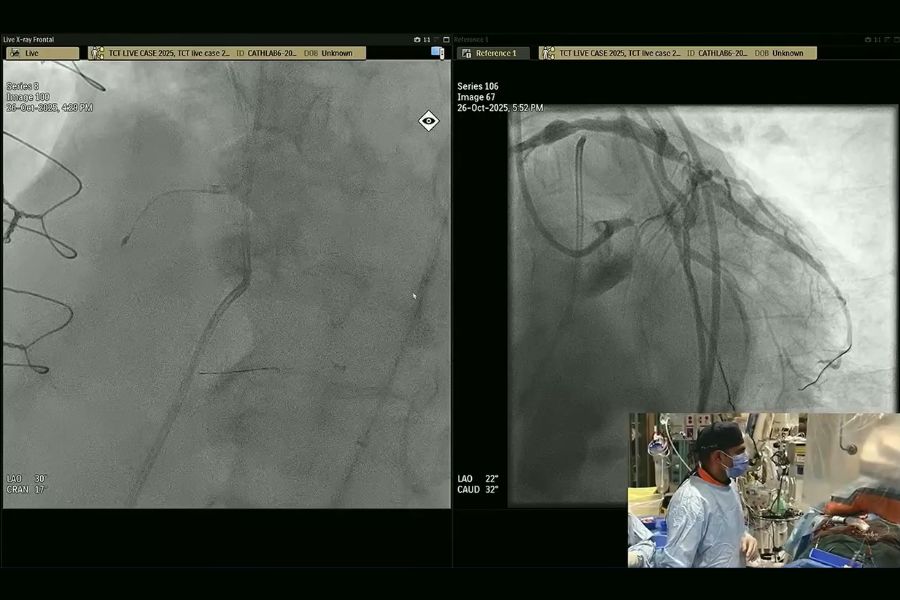

Dr. Sanjog Kalra performed intravascular imaging in complex PCI during his live case session at the 2025 TCT Conference. (Photo: Transcatheter Cardiovascular Therapeutics Conference/Cardiovascular Research Foundation)

During his session at TCT, conference attendees watched as Dr. Kalra and his team performed intravascular imaging in complex PCI.

The procedure involved treating a man in his early 60s who had three of his four major heart vessels blocked.

"The patient came to the table with a confluence of three things: His heart pumping function was weak, his coronary anatomy was super complicated and he had a bunch of medical problems," says Dr. Kalra.

At the end of the procedure, the team successfully restored blood flow to the patient's heart vessels.